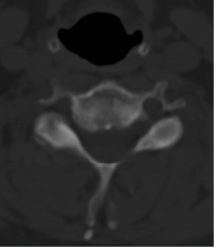

Pre-op CT demonstrates right C5-6 uncovertebral joint osteophyte causing foraminal stenosis but minimal facet arthrosis.